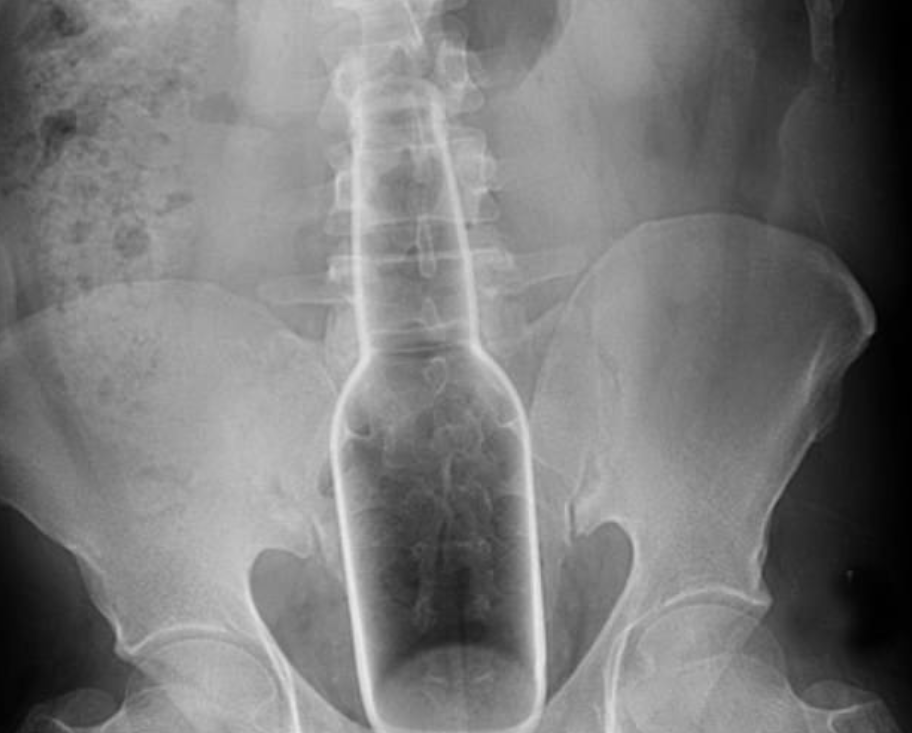

▼也曾有醫生在患者的直腸內取出完整的瓶子!